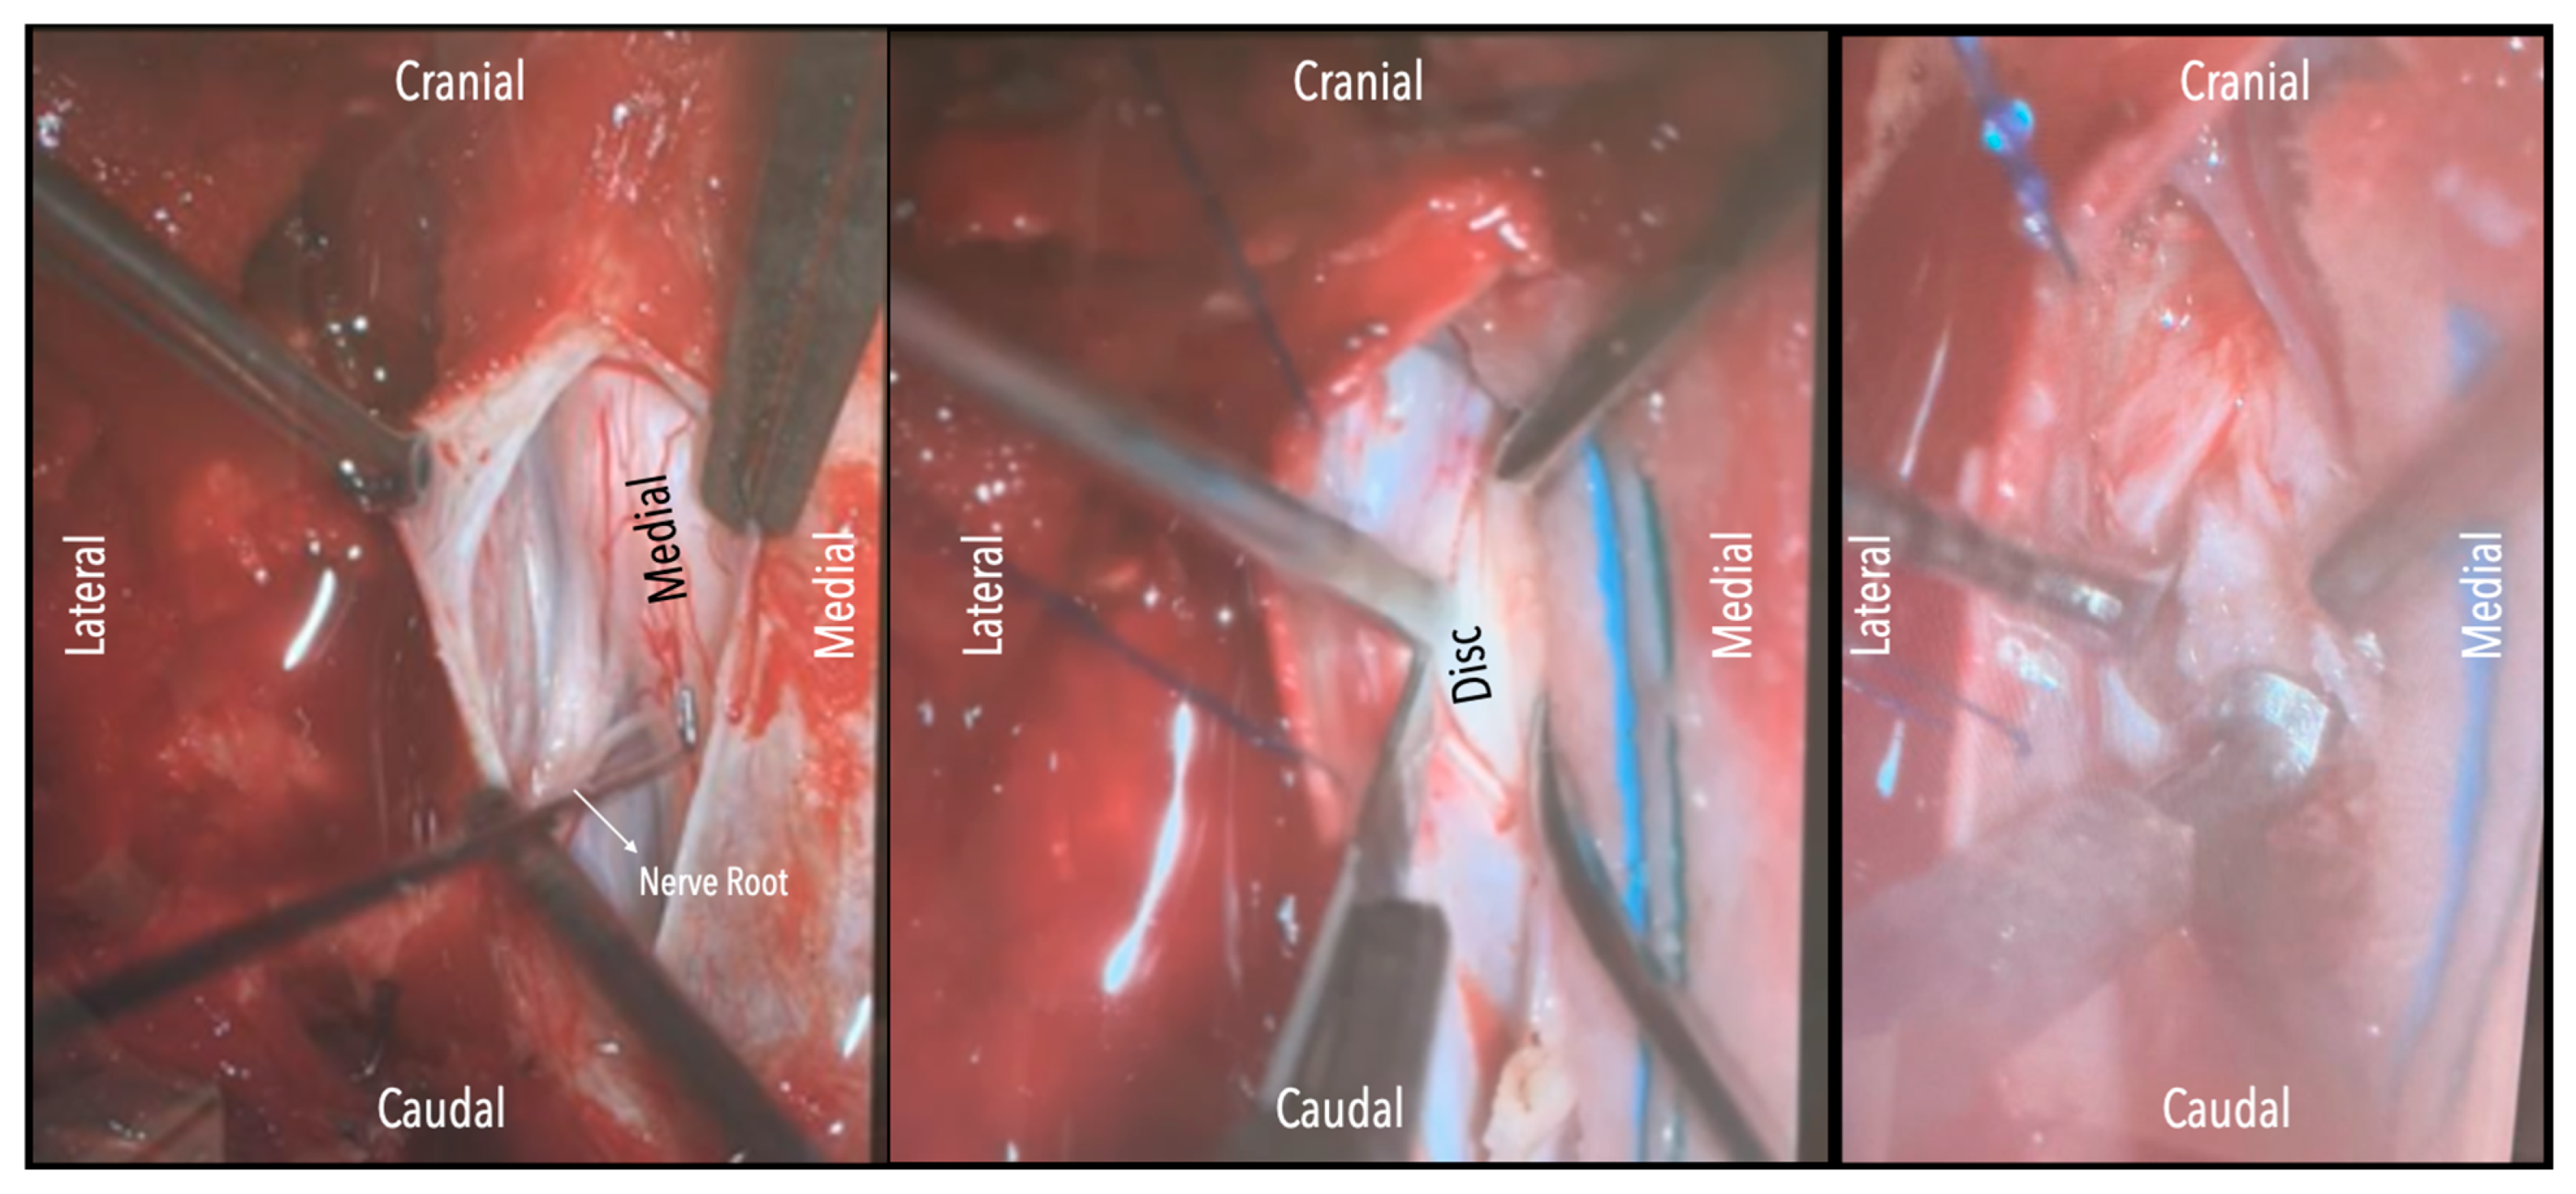

Figure 2. (a). Surgical field under microscope magnification. A: Opening of dura with no. 15 blade. B: Release of CSF. Following this, the table was tilted contralateral to the disc side to allow the cord (see annotation in image on the left) to slowly drift away. The dentate ligament, appearing as a thickening of the arachnoid, can be identified and dissected with microscissors. C: The nerve root is evident. If required, it could be sacrificed intramurally (see dashed line and annotation in image on the left side) with microscissors after being coagulated with bipolar diathermy. (b). Intraoperative microscope view of the same case. Right-sided disc. A: The calcified disc is evident after gentle gravity-retraction of the cord. B: A hockey stick bone scalpel (MISONIX). C: Watertight closure of dorsal dura.

Figure 3. Intraoperative microscope view. Left-sided disc. Left: After opening the dura mater, the nerve root and cord are evident. Middle: Following drainage of CSF, dissection of the dentate ligament and gravity retraction, a micro-pattie is applied on the lateral aspect of the cord and a penfield microdissector is used to gently retract the cord, and the disc becomes evident. Right: Discectomy is carried out with a hockey stick bone scalpel.

A wide en bloc laminectomy was performed at the disc level and one level above and below using a Misonix bone scalpel. This was followed by ipsilateral superior and inferior facetectomies and complete pediculectomy to establish an oblique and spacious working corridor toward the ventral spinal canal (Figure 1). Under the operating microscope, the dura was opened in the midline with a no. 15 blade, and the arachnoid was incised sharply. CSF was allowed to drain passively for 10–15 min to reduce intradural pressure and promote relaxation of the spinal cord. The table was then tilted approximately 6–10 degrees to the contralateral side to allow for gravity-assisted displacement of the cord away from the operative field (Figure 2a,b and Figure 3).

In three of the seven cases, the exiting nerve root at the level of the herniation was ligated due to poor visualization and transected extradurally to improve access. In the remaining four patients, the nerve root was either preserved or dissected intradurally using isocool bipolar diathermy and microsurgical scissors. With gentle medial retraction of the cord under gravity and protection using a micro-patty, the calcified disc was exposed. The ventral dura, when intact, was incised sharply and dissected from the disc surface where possible (Figure 2a,b and Figure 3). Disc removal was performed using a hockey-stick-shaped Misonix bone scalpel with constant irrigation, guided by intraoperative neuronavigation. The disc material was resected to a depth of 1–2 mm beyond the posterior vertebral wall to ensure adequate decompression. A second O-Arm spin was routinely performed following discectomy to confirm satisfactory decompression, especially given the limitations of the postoperative MRI due to the metal artefact (Figure 4, Figure 5 and Figure 6).